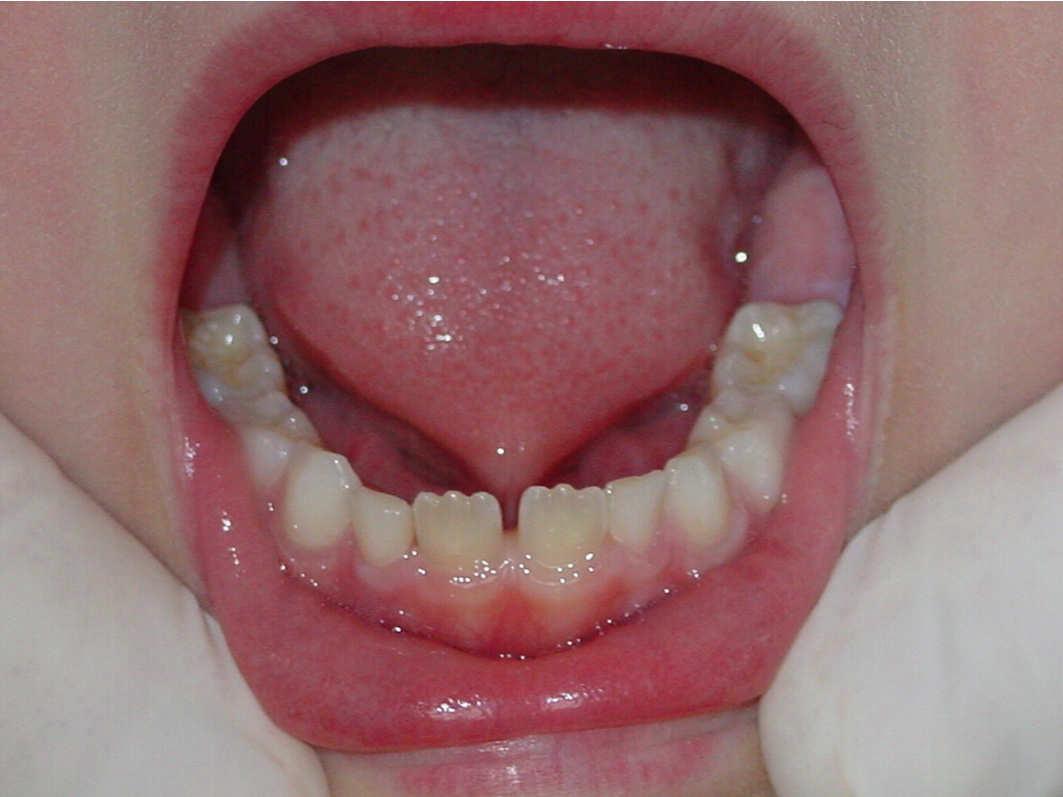

Diode Laser 810nm

Power: 2.5 Watt,

Pulsed 50 Hz ,Fibre 400 micron

2

Dott. Stefania Cristalli